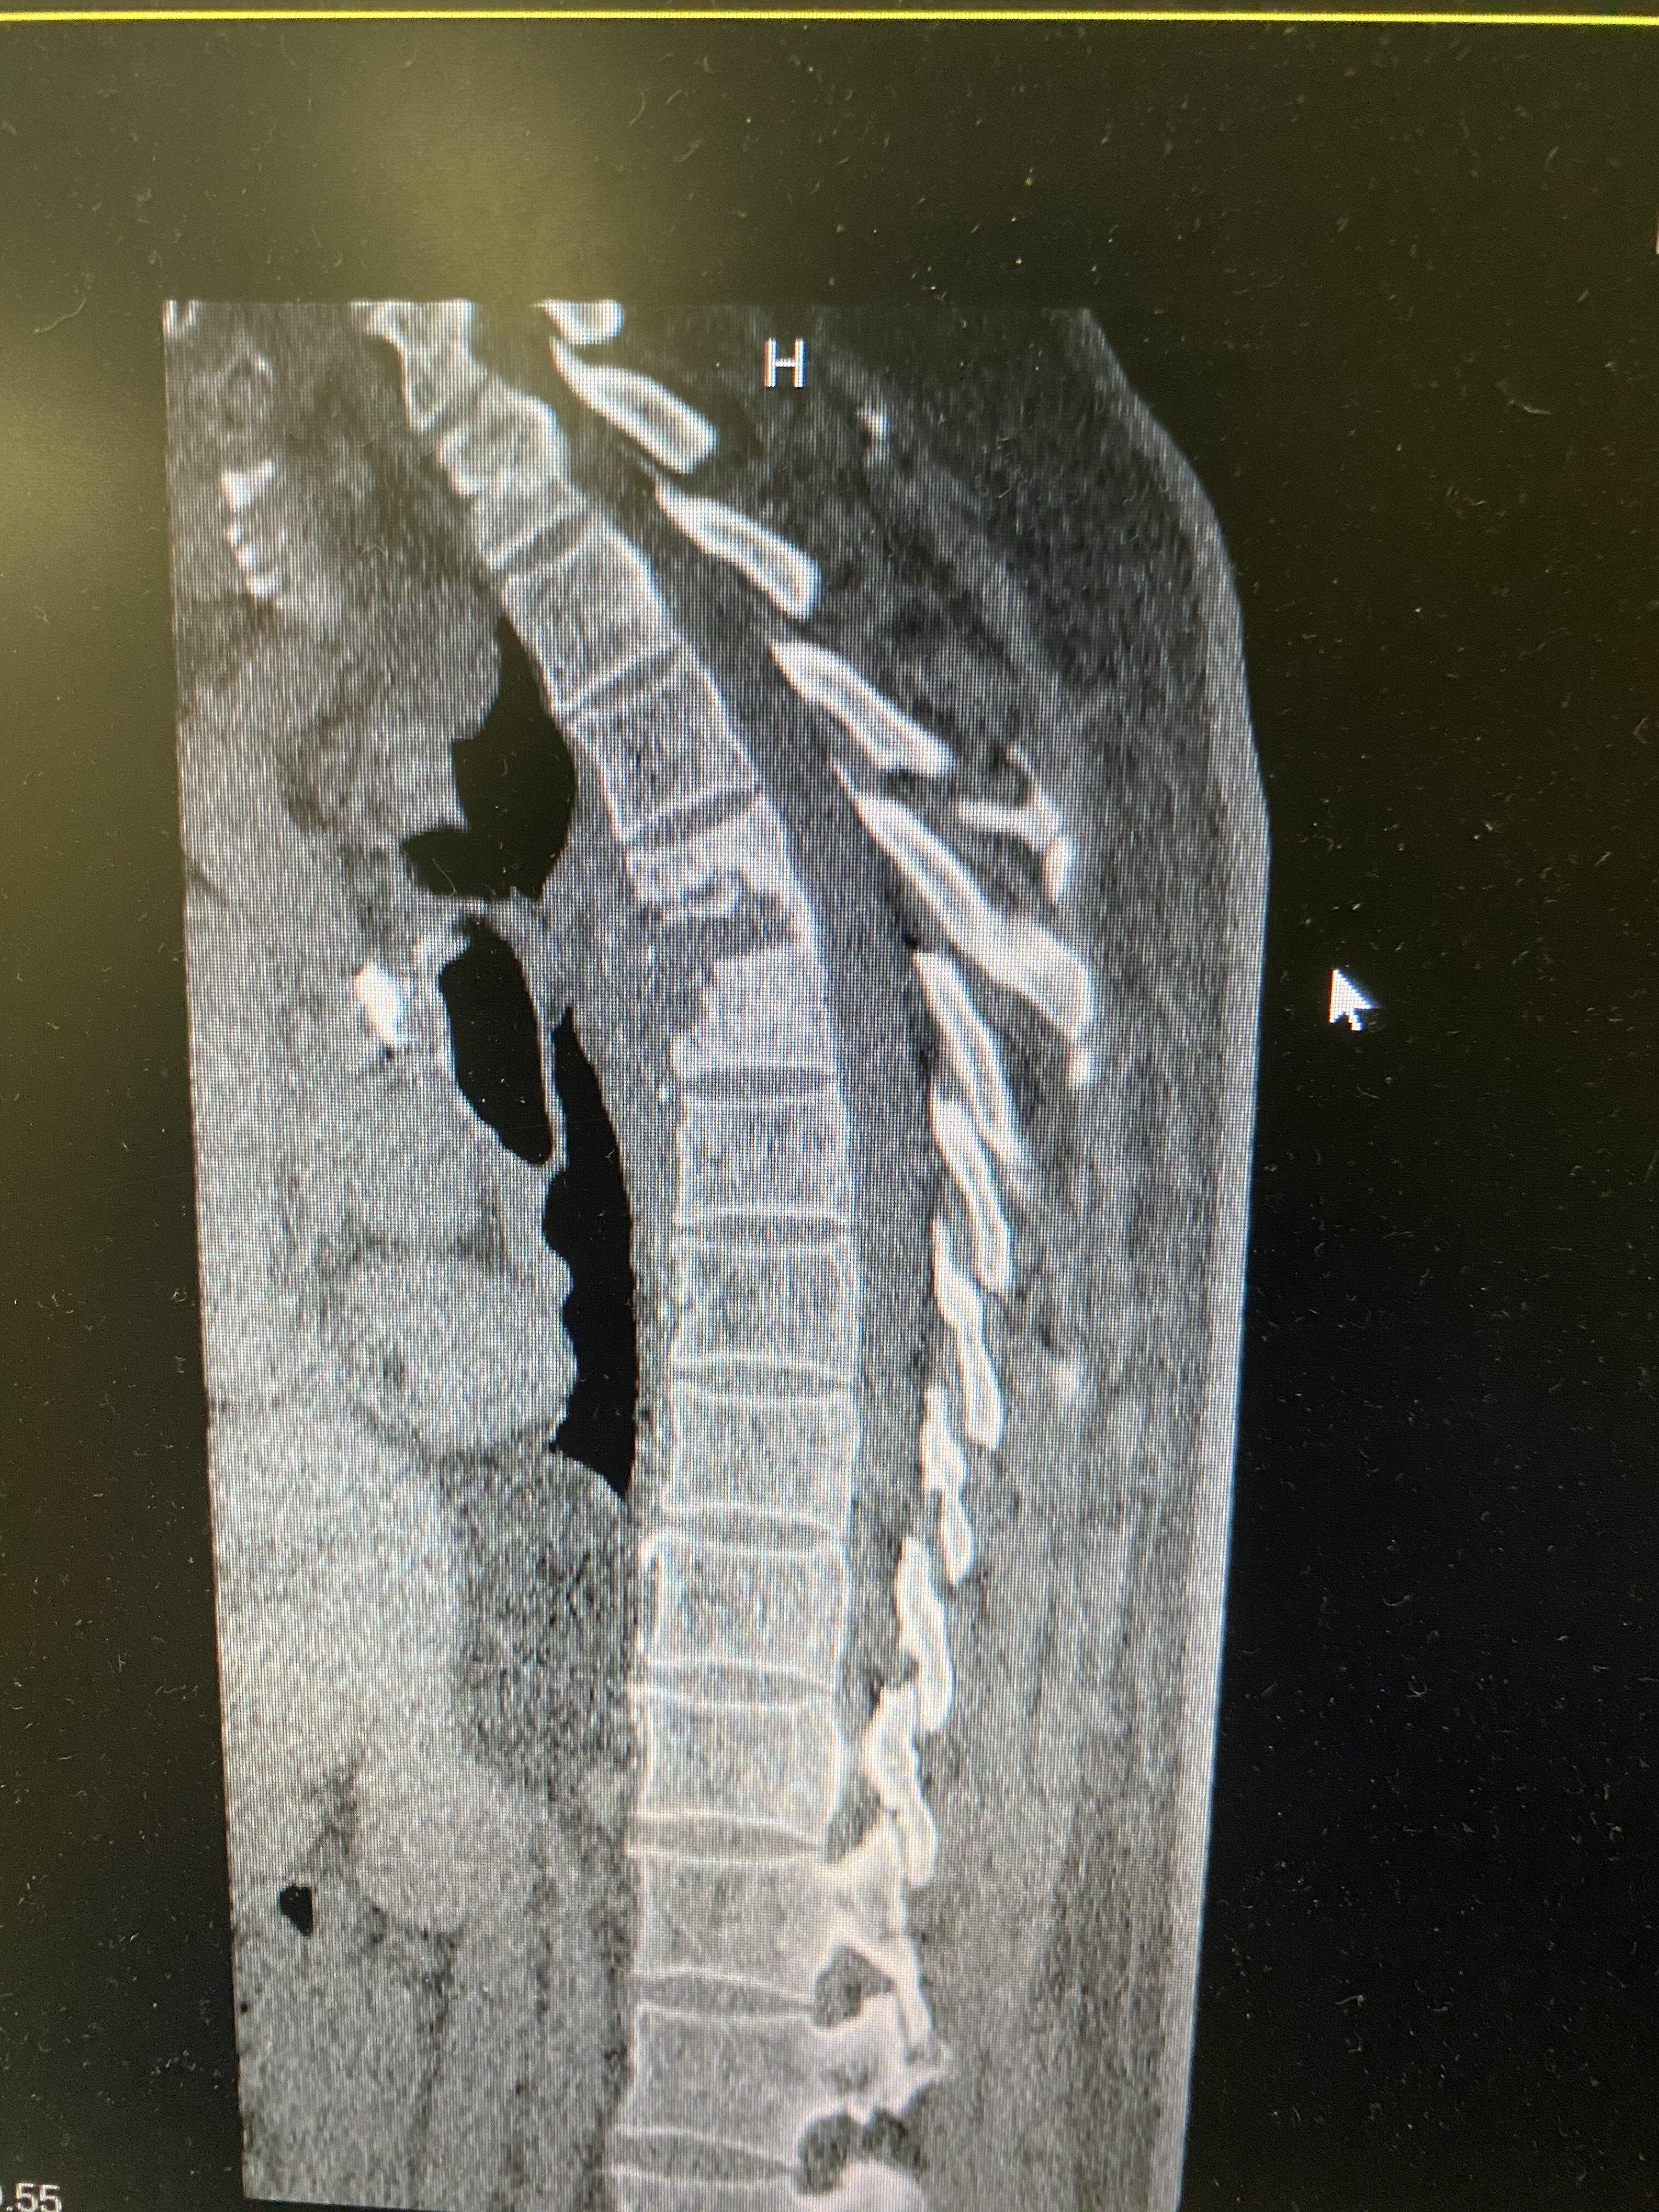

该患者老年男性,肺结核,低热乏力行抗结核治疗两个月以后,持续胸痛、背痛,无法缓解。做胸椎核磁共振和CT考虑胸椎结核,椎体椎间盘结合病灶,椎旁脓肿形成,椎体破坏明显。